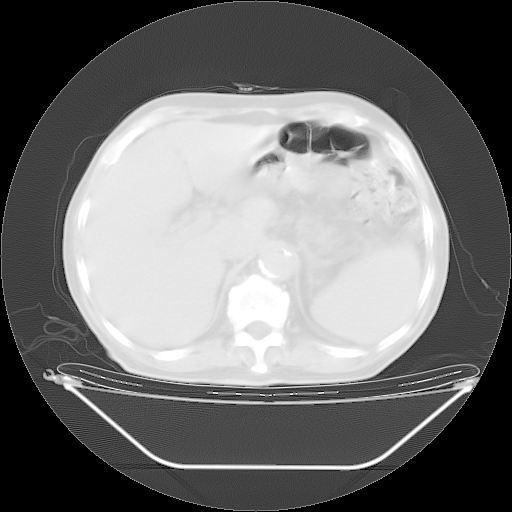

今天复查肺部CT,发现双肺广泛磨玻璃样改变。所以我把3月19日和5月9日相隔50天的肺部CT上传。请大家会诊。

5月9日肺部CT(在4月27日齐鲁医院肺部CT描述部分肺组织磨玻璃样改变,12天后肺组织广泛磨玻璃样改变)

2009年5月9日肺部CT

大致读了系列胸部CT:纵隔窗无明显异常,肺窗:从4、27至今:主要是双肺中下野外带可见毛玻璃样改变,目前处于急性肺泡炎阶段,至于原因考虑1、结替组织或胶原血管性疾病所致?2、恶性疾病如恶组在肺部所致的表现或细支气管肺泡癌?3、药物或其它原因如肺蛋白沉着症所致肺泡炎目前不太可能?总之,明天就去请我院的呼吸科、感染科、血液科和临免专家会诊哈。